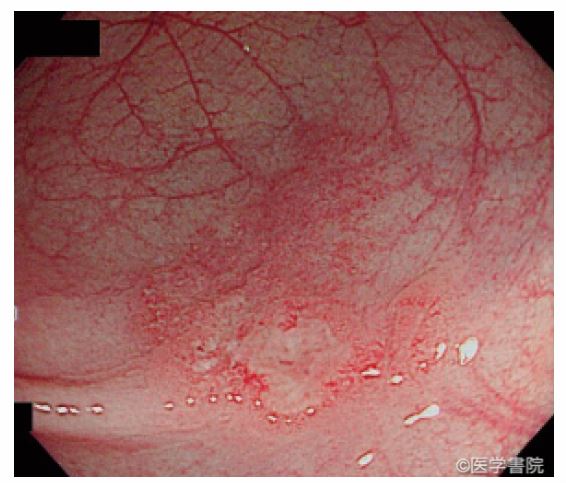

高悪性度癌は、その多くが進行癌で見つかります。下記の写真は極めて珍しい「初期の低分化粘液癌」の報告です。

韓国からの報告(初期の印鑑細胞癌) 秋田赤十字病院からの報告 (初期の低分化癌)

遺伝子解析から、これらの癌の起源は「腺腫ではなく過形成ポリープらしい」というのが、今回の話なのですが、形態からは予想された話です。高悪性度癌も過形成ポリープ(SSL)も境界が不明瞭で、正常粘膜に近く炎症のように見えるのが特徴です。